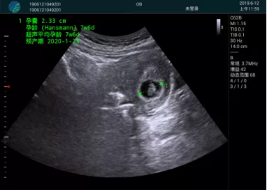

便攜超聲引導(dǎo)下人流術(shù)

病例一:

清晰顯示孕囊,通過軟件包計算孕齡7w+6d

M20實時引導(dǎo),術(shù)中清晰顯示孕囊被破壞和抽吸針的過程,清晰顯示吸引針

抽吸結(jié)束后縱切子宮,孕囊已被完全抽吸,未見明顯殘留

橫切子宮,發(fā)現(xiàn)右側(cè)宮腔靠近宮角處有少許脫模樣殘留

M20引導(dǎo)下,抽吸針找到右側(cè)宮角處再次清掃

二次抽吸后再次進行超聲檢查,宮腔未見殘留,宮腔線清晰顯示

超聲引導(dǎo)下可視化人流是技術(shù)安全性的保障,一般對人流術(shù)設(shè)備預(yù)算不高,M20具備婦產(chǎn)科軟件包,且穿透力圖像質(zhì)量好,既滿足人流引導(dǎo)需要,也可用于床旁超聲的需求。